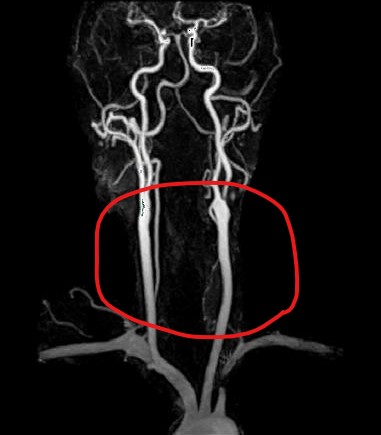

MRA(Magnetic Resonance Angiography)는 자기공명영상(MRI) 기술을 활용하여 혈관의 상태를 촬영하는 검사입니다. 이 방법은 X선을 사용하지 않고 강력한 자기장과 라디오파를 이용해 혈관 내부의 이미지를 생성합니다. 특히 경부혈관 MRA는 목 부위의 혈관, 예를 들어 경동맥과 같은 주요 혈관의 상태를 평가하기 위해 사용되며, 혈관의 구조적 이상, 협착, 동맥류 등을 평가할 수 있습니다.

경부혈관 MRA(Magnetic Resonance Angiography)는 자기장과 라디오 파동을 사용하여 혈관의 이미지를 생성하는 비침습적 검사 방법입니다. 이와 달리, 경동맥 초음파는 음파를 사용하여 혈관의 혈류와 구조를 평가하는 검사로, MRA보다 저렴하고 접근성이 좋지만, MRA가 제공하는 세부 이미지에는 미치지 못합니다. MRA는 특히 혈관의 이상을 정밀하게 평가해야 할 때 사용되며, 경부혈관 포함 여러 부위의 혈관을 동시에 평가할 수 있습니다. 경부혈관 MRA는 특정 상황에서 필요하며, 모든 환자에게 일반적으로 시행되는 검사는 아닙니다.

MRA는 한 눈에 전체 그림을 볼 수 있다는 것이 큰 장점이지만 하나하나의 혈관을 자세하게는

관찰할 수 없다는 단점이 있습니다